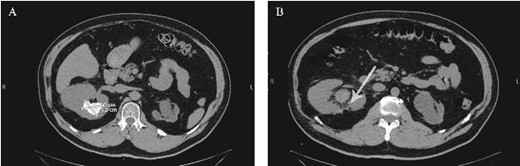

A 62-year-old man presented to the urology clinic complaining of recurrent right flank pain and an ultrasound report of a right kidney stone. Patient had a history of left open pyelolithotomy performed twice due to left kidney stone, which led to left atrophic kidney. He had a history of right open partial nephrectomy due to renal mass highly suspicious of renal cell carcinoma on CT done 4 years ago. He had a medical history of type 2 diabetes mellitus, hypertension, dyslipidemia, and stage I chronic kidney disease (CKD). A new noncontrast CT showed left atrophic kidney and right huge kidney stone of 4.5 × 4 cm in the posterior part of the upper calyx (Fig. 1). Patient was offered percutaneous nephrolithotomy (PCNL), but he refused due to the fear of possible bleeding complications. He preferred multiple session flexible ureteroscopy with holmium laser lithotripsy. The patient was pre-stented 2 weeks before the first session.

(A) Preoperative non-contrast CT scan showing a renal stone measuring 4.5*4 cm. (B) Postoperative non-contrast CT scan. The arrow points to the area from which the pseudoaneurysm most-likely originated postoperatively.